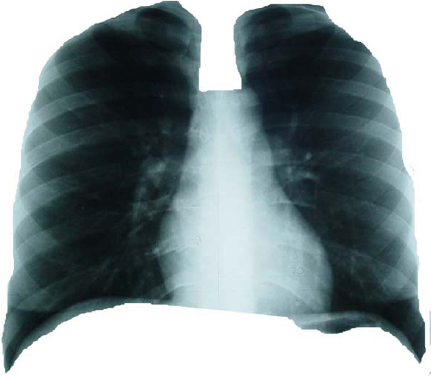

Isla 1: Isla radiopaca a la observación, limitada por los contornos dibujados en la placa detórax del ventrículo y aurícula izquierda, botón aórtico y aurícula derecha, correspondiente a la silueta cardíaca. (Ver Figura 1). Isla 2: Isla radiolúcida a la observación. Está definida por:

Isla 3: Superposición de la isla 1 con la isla

2. Objeto fractal total. Cavidad torácica completa (Ver Figura 3).

Figura 1. Composición de la radiografía de tórax: Isla 1

Figura 2. Composición de la radiografía de tórax: Isla 2.

Figura 3. Composición de la radiografía de tórax: Isla 3.